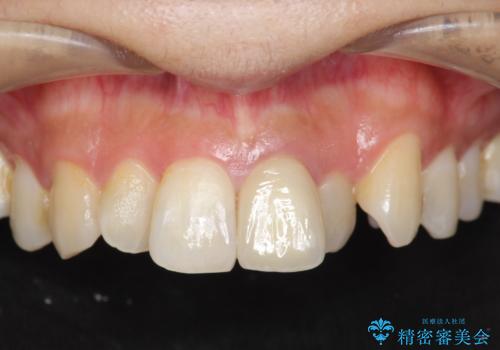

- 虫歯の多発、歯周病治療の治療を希望され、全体的な治療を提案した症例です。

重度の深い虫歯・歯周病の歯が散見されますので、まずは残せる歯と残せない歯の見極めを行い、残せる歯は歯周外科手術を用いて歯を可能な限り残すことを計画します。

長期的な予後を見込むには、虫歯の徹底的な除去・歯周ポケットの除去・噛み合わせの安定・適合の良い補綴物の要件を満たすことが重要です。

残せる歯と残すことが難しい歯の選別、ブリッジ・インプラントを適宜判断し補綴処置を行っていきます。

仮歯の期間も長期間となりましたが、ブラッシング指導も行いモチベーションも上がり、長期的な予後を見込める状態となりました。